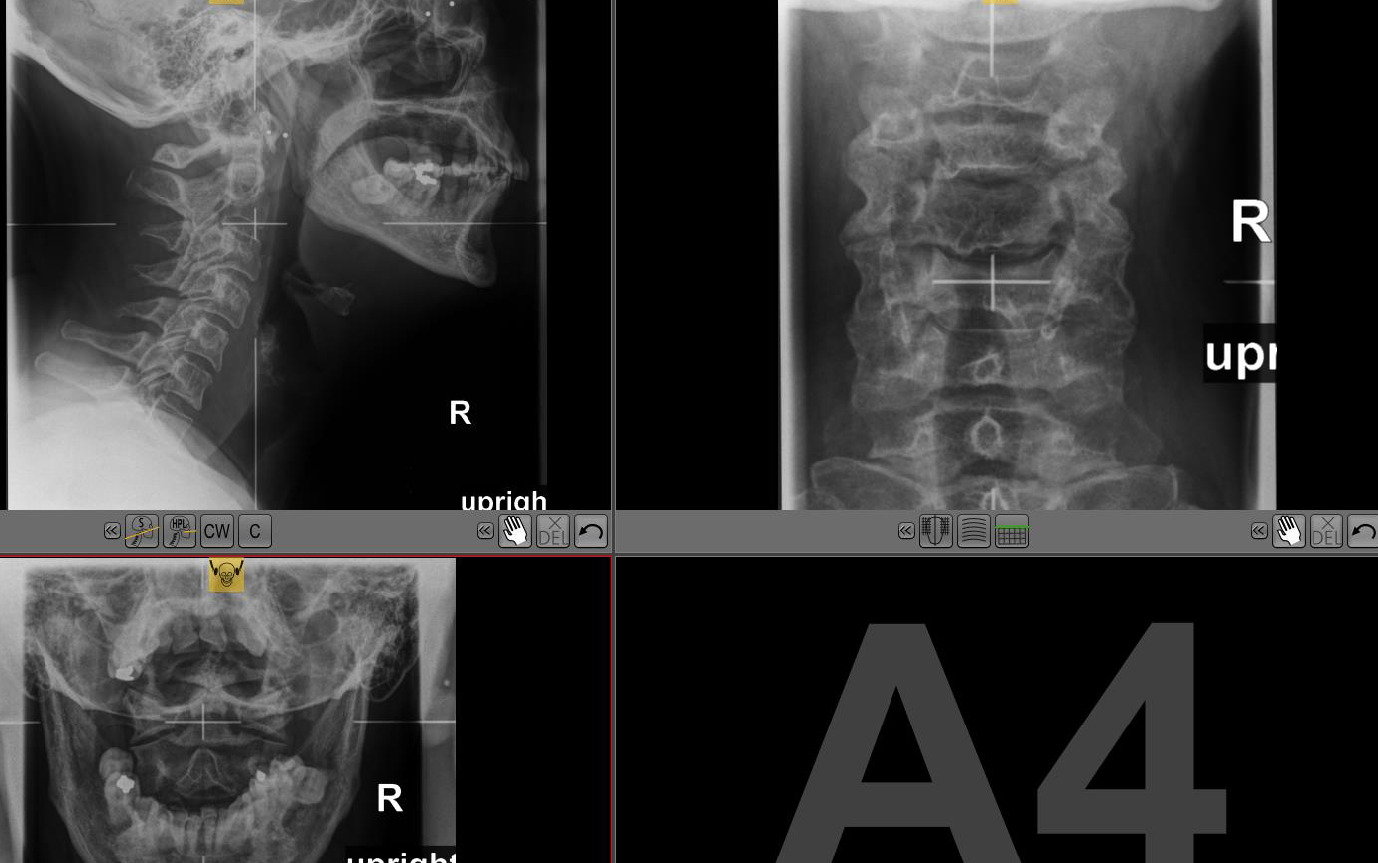

Figure 7 depicts a typical 3 view X-ray series; Figure 8 depicts multiplanar reconstruction (MPR) view using a single CBCT scan on the same patient.